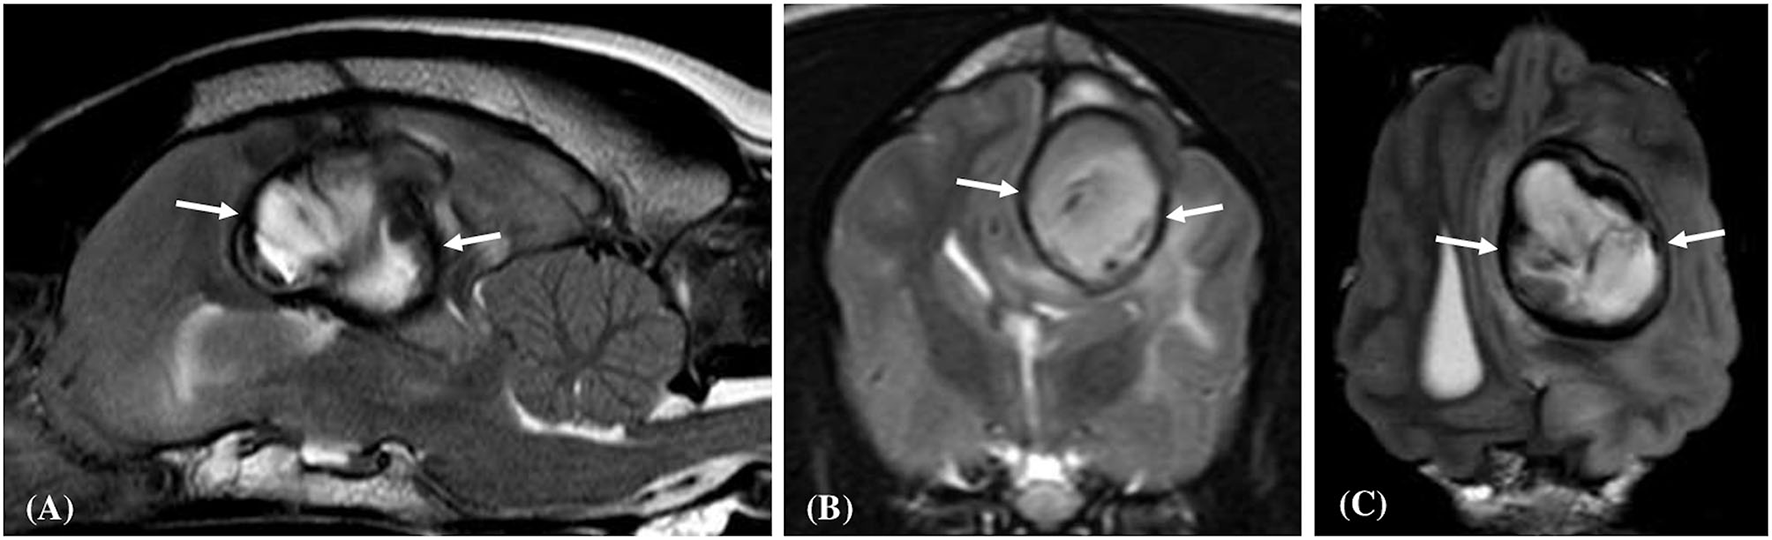

Figure 3

Left parasagittal (A), transverse (B), and dorsal (C) plane T2- weighted images of a dog (Case 8) with a large well-defined intracranial intra-axial hematoma affecting the white matter of the left parietal lobe. Note the circumferential nature of the thin hypointense rim (white arrows) in all three planes. Additionally, the lesion induces a marked mass effect resulting in transtentorial herniation, subfalcine herniation and compression of the left lateral ventricle.